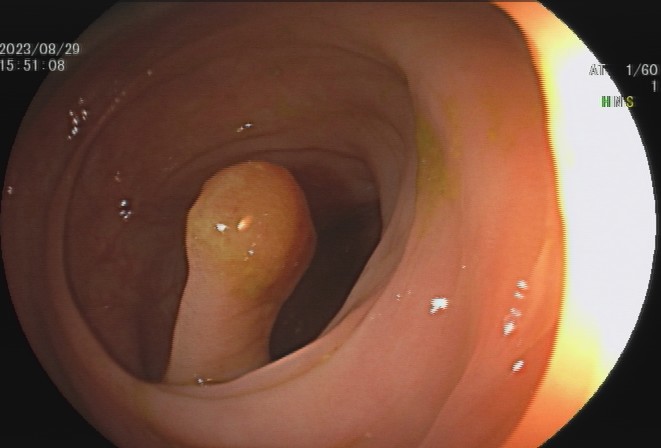

肠息肉是指突出于肠腔表面的隆起,在没有确定病理性质前统称为息肉,其发生率通常随年龄增加逐渐上升,病变部位以结直肠多发,与结直肠癌的发病有密切关系。

少数患者会发生便血,而结肠息肉很多的患者也可能会发生腹泻、黏液便、腹痛等症状,但这些症状无特异性,因此要确诊结肠息肉主要依赖结肠镜等检查,多数患者是在体检或因其他疾病做结肠镜时才被发现。

95%以上的结肠癌是从结肠息肉一步步转变而来,因此,结肠息肉一旦发现应该及时切除。发现息肉和早期肠癌,在内镜下就可以把这颗“定时炸弹”切除,创伤也小,对预期寿命几乎没有影响。